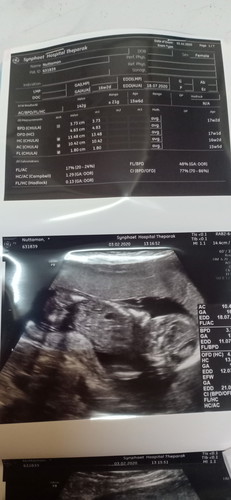

16wค่ะแข็งแรงดีแต่หนูนแนคว่ำแบบนี้จะเพศหญิงรึชายนะ